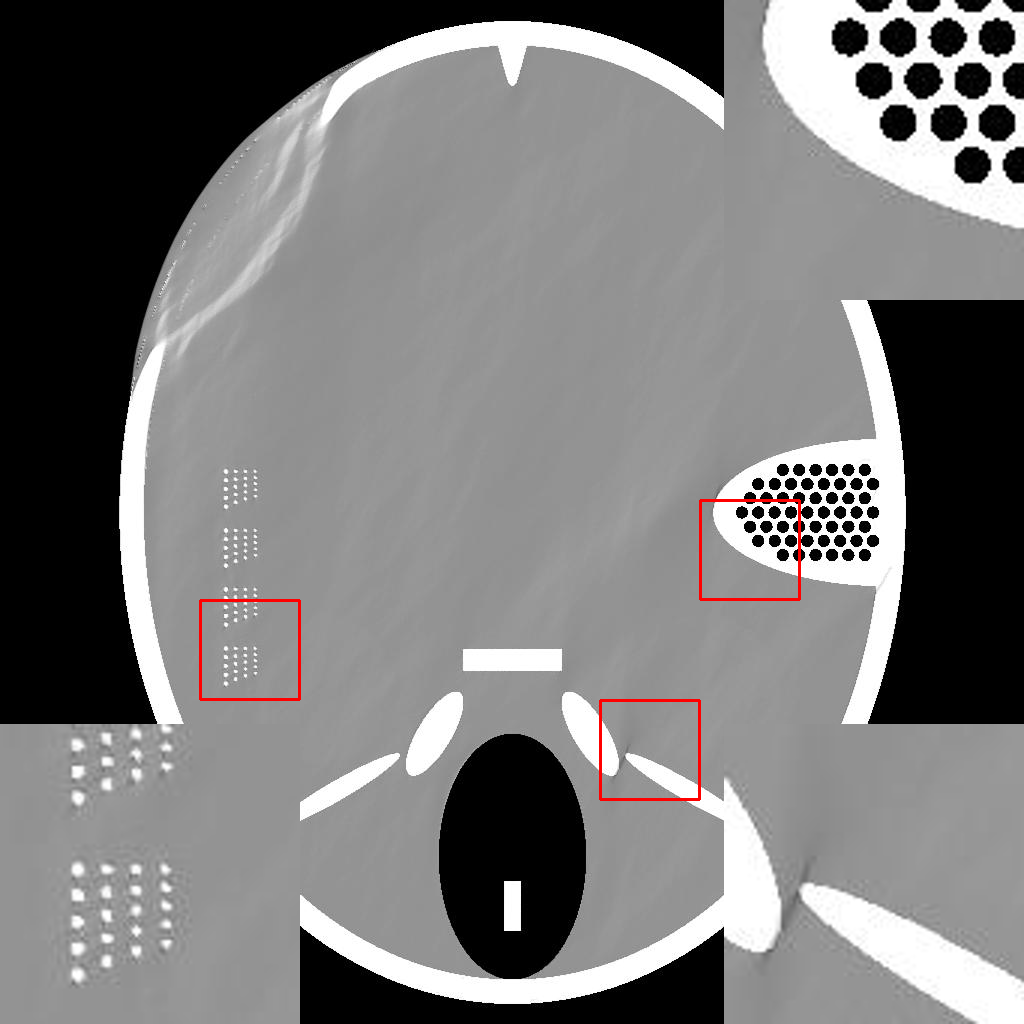

In order to demonstrate the efficacy of the RBP connection and show the details of the RBP-DIP’s reconstruction process, the procedure of a limited-angle CT reconstruction is shown in Fig.2. Its first row shows the reconstruction outcomes of varying iterations, while the second row shows the corresponding input of the U-net, which has been updated through the RBP connection. Here, the number of views is set to , uniformly distributed from to . This scenario presents a challenging limited-angle CT reconstruction problem.

In the first iteration, as depicted in Fig.2a, the input image undergoes an update via the RBP connection prior to being fed to the U-net. Thus, this input is the normalized first iteration output of the implemented IR algorithm (normalized back projection image in our case). The output appears completely randomized since the entire neural network is randomly initialized.

In the 10th and 20th iterations (Fig.2b and Fig.2c), the DIP property effectively expedites the recovery of the object over its support. Of note are lack of artifacts commonly caused by having missing views in the data. The input images highlight the region which can be relatively accurately reconstructed by conventional IR methods. This can be used to guide the model in the later iteration. In our experiment, the model capitalizes on the input images more when reconstructing the top left and the bottom right parts of the image, while relying predominantly on the DIP property for the reconstruction of the top right and the bottom left parts.

In the 2000th iteration, as depicted in Fig.2d, the reconstruction result becomes relatively artifact-free. At this stage, the input image of the U-net primarily emphasizes the edges to help the method improve the supporting area. Moreover, the RBP connection can rectify artifacts specific to convolutional neural networks. Evidence of this can be observed in the second row of Fig.2c, Fig.2d, and Fig.2e, which display distinct horizontal and vertical patterns. These patterns are mainly caused by the convolution operation in the U-net. In other words, the DIP and RBP parts of the proposed framework are able to mutually rectify each other’s errors. Consequently, a high-quality reconstruction result is attainable, as shown in Fig.2e.